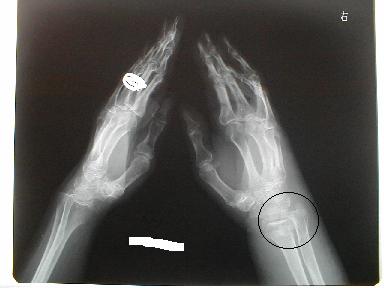

1月23日整復固定 正面像

側面像